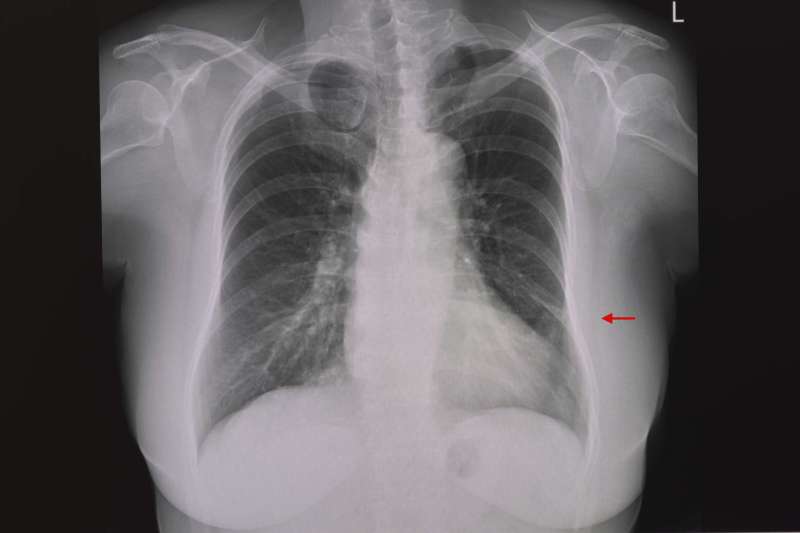

Signs of a punctured lung can also be seen on a chest x-ray, where black areas of air will be visible between the lung and the chest wall.

Chest x-rays (pictures of your lungs) are the first step in diagnosing atelectasis. Your doctor may use a computed tomography (CT) scan to get more detailed images if necessary.

A pneumothorax is a collapsed lung. A pneumothorax occurs when air enters the pleural cavity. It is the space between the outside of the lung and the rib cage. A small pneumothorax can